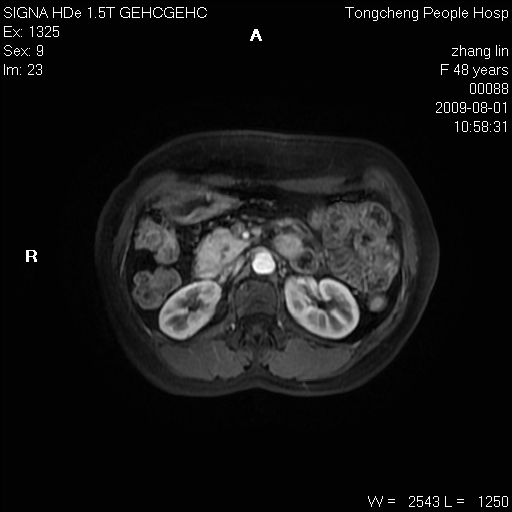

女,48岁。健康体检,彩超发现右肾占位性病变。平素健康。

临床诊断:右肾占位性病变,性质待定(囊肿?肿瘤?)。

上中腹部mr平扫+增强扫描,图像如下:

右肾上极见一类圆形病灶,t1wi呈等信号t2wi呈等高混杂信号,三期增强无强化,边界清---考虑囊肿出血。

同反相位均表现为等信号,病变无强化,考虑含蛋白的囊肿可能,弥散加权相或许有些帮助,

慢性胆囊炎